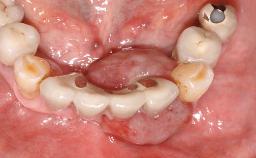

Surgical treatment of a 32-year old, healthy and non-smoking female who required removal and replacement of a lateral maxillary incisor due to internal root resorption. The inflammatory process caused a reduction of the crestal bone level on the distal side of the tooth necessitating an augmentation procedure to meet the patient's high esthetic demands. Due to the high smile line, the thin soft-tissue biotype and triangular-shaped teeth several esthetic risk factors are present.

After flapless tooth removal and a healing period of 6 weeks a diameter-reduced two-piece implant is placed. The bone defect on the facial aspect is corrected with a contour augmentation using autologous bone chips covered with DBBM particles and a collagen membrane according to the Guided Bone Regeneration (GBR) approach.